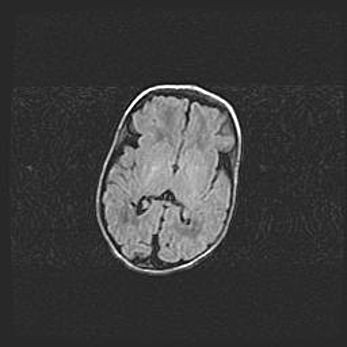

Сообщающаяся гидроцефалия. Кистозная энцефаломаляция головного мозга.

Возраст: 3 месяца 4 дня

Вес: 3100 г

Пол: женский

Окружность головы: 34 см

Срок гестации: 31 неделя

Кистозная энцефаломаляция головного мозга - одна из форм поражения головного мозга в детском возрасте. Характеризуется возникновением множественных и распространённых кист в коре, белом веществе и подкорковых образованиях головного мозга у плодов, новорождённых и детей раннего возраста. Развитие кистозной энцефаломаляции связано с внутриутробной асфиксией и гипотонией, родовой травмой, тромбозом синусов, пороками развития сосудов, инфекциями, сепсисом и другими причинами. Наиболее значимые инфекционные агенты: вирусы простого герпеса, цитомегалии, краснухи, токсоплазмы, энтеробактерии, золотистый стафилококк и другие.